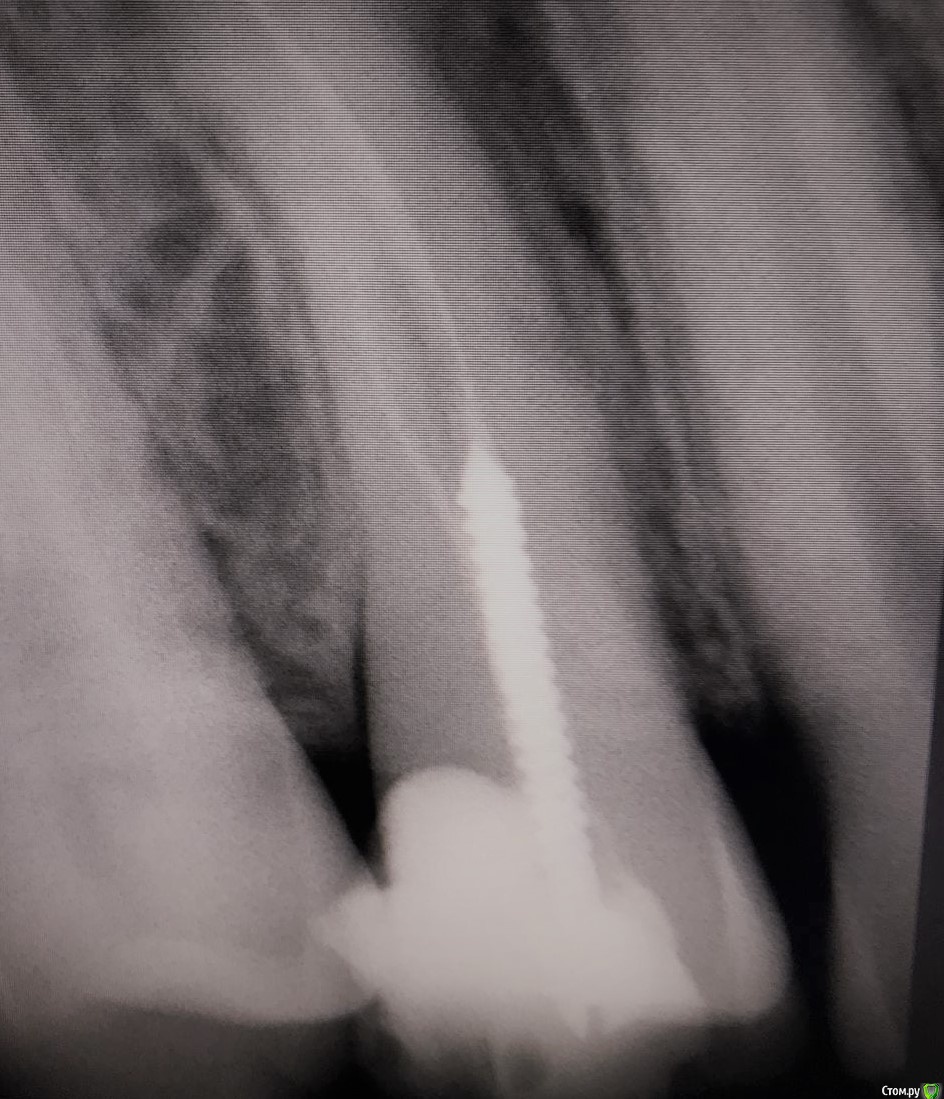

1586Doc Опубликовано 8 февраля, 2020 Поделиться Опубликовано 8 февраля, 2020 5 месяцев назад обратилась пациентка с симптоматикой периодонтита. Оценили, попробовали. Пломбировка вертикалка. 5 месяцев и контроль, боли нет, подвижности тоже. 2 Ссылка на комментарий

1586Doc Опубликовано 10 февраля, 2020 Автор Поделиться Опубликовано 10 февраля, 2020 (изменено) А где контроль на сегодня? При таком качестве снимков оценить будет тяжело.первые 2 фото снимки 9 месяц назад, до ревизии Изменено 10 февраля, 2020 пользователем 1586Doc Ссылка на комментарий

1586Doc Опубликовано 17 января, 2021 Автор Поделиться Опубликовано 17 января, 2021 первые 3 фото, ретрит 14 зуб4.5 фото 45 зуб. 4 Ссылка на комментарий

1586Doc Опубликовано 12 мая, 2021 Автор Поделиться Опубликовано 12 мая, 2021 ретрит зубов 15.14.26 и контроль клкт через 6 месяцев Ссылка на комментарий